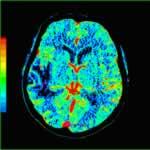

急性腦缺血

臨床上 CT 廣泛套用 於腦卒中檢查以除外腦出血抑或腦缺血 ,其中,後者占85%,大部分患者在發病 6 小時之內 CT往往表現正常或不典型而誤診或漏診。